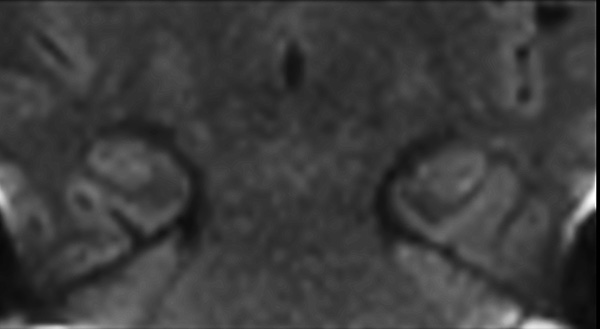

Comprehensive Brain imaging at 1.5T

Used Solution

• Clinical Application